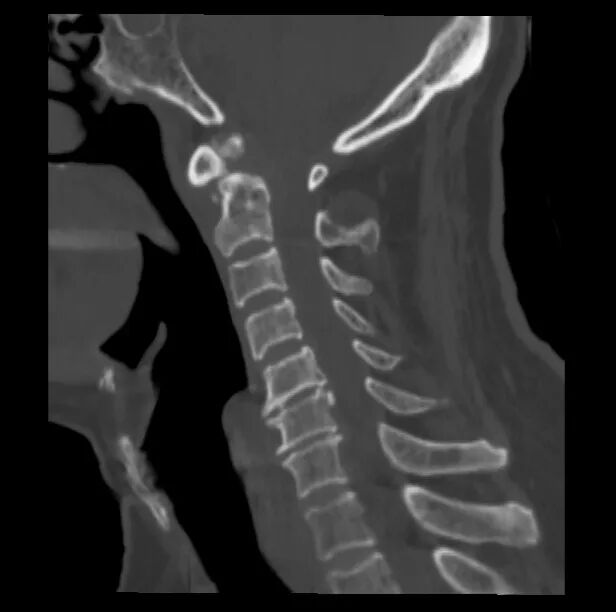

▲术前

此次接受手术的患者年事已高,基础疾病较多,身体耐受度低、手术风险显著高于普通患者。若保守治疗,脱位难以复位,脊髓压迫持续加重;若手术治疗,则对术者精准操作、麻醉管理、围手术期护理均提出极高要求。